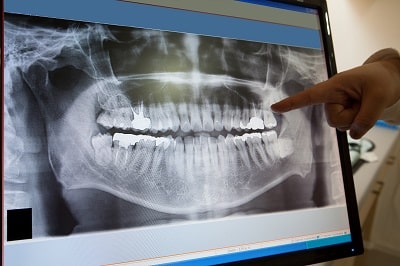

Oral surgery successfully treats many different health conditions and diseases. Your dentist may also recommend oral surgery to correct the appearance of teeth and the surrounding bone structure. While the prospect of oral surgery can seem daunting, you will likely receive sedation to ensure comfort during the procedure. Here are some common types of oral surgery and what you can expect when visiting your oral surgeon.

Extractions are often performed on wisdom teeth before they can cause damage to surrounding teeth. It’s usually best to have wisdom teeth removed early in life to prevent complications. When teeth begin to push against one another, it can create overcrowding, misalignment, and infection. It may also be necessary to remove some teeth to make room for future orthodontic work.

Dental Implant Surgery

This surgery replaces missing teeth with artificial replicas that blend in seamlessly with other teeth. Dental implant surgery consists of two stages. First, a titanium post is surgically placed into the jaw to serve as an anchor for a custom prosthesis. Once the implant has healed, a crown, bridge, or denture can be attached.

Since the bones supporting the teeth require stimulation to continue to grow, missing teeth can lead to bone deterioration. Dental implant surgery can help reduce further bone loss by restoring normal function and improve the aesthetics of your smile.